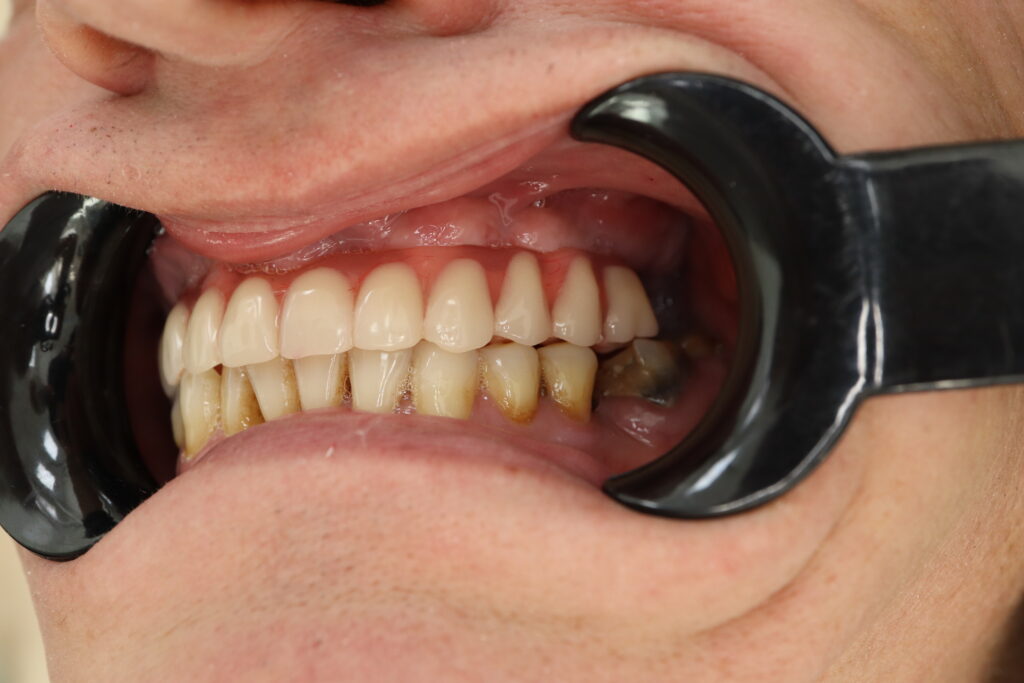

Результат

После консультации было принято решение об удалении зубов на верхней челюсти, которые находились в неудовлетворительном состоянии

и проведении комплексной имплантации по системе All-on-4.

Стоимость всего комплекса: 3500 USD (цена указана ориентировочно по курсу НБРБ на день оплаты)

результат протезирования